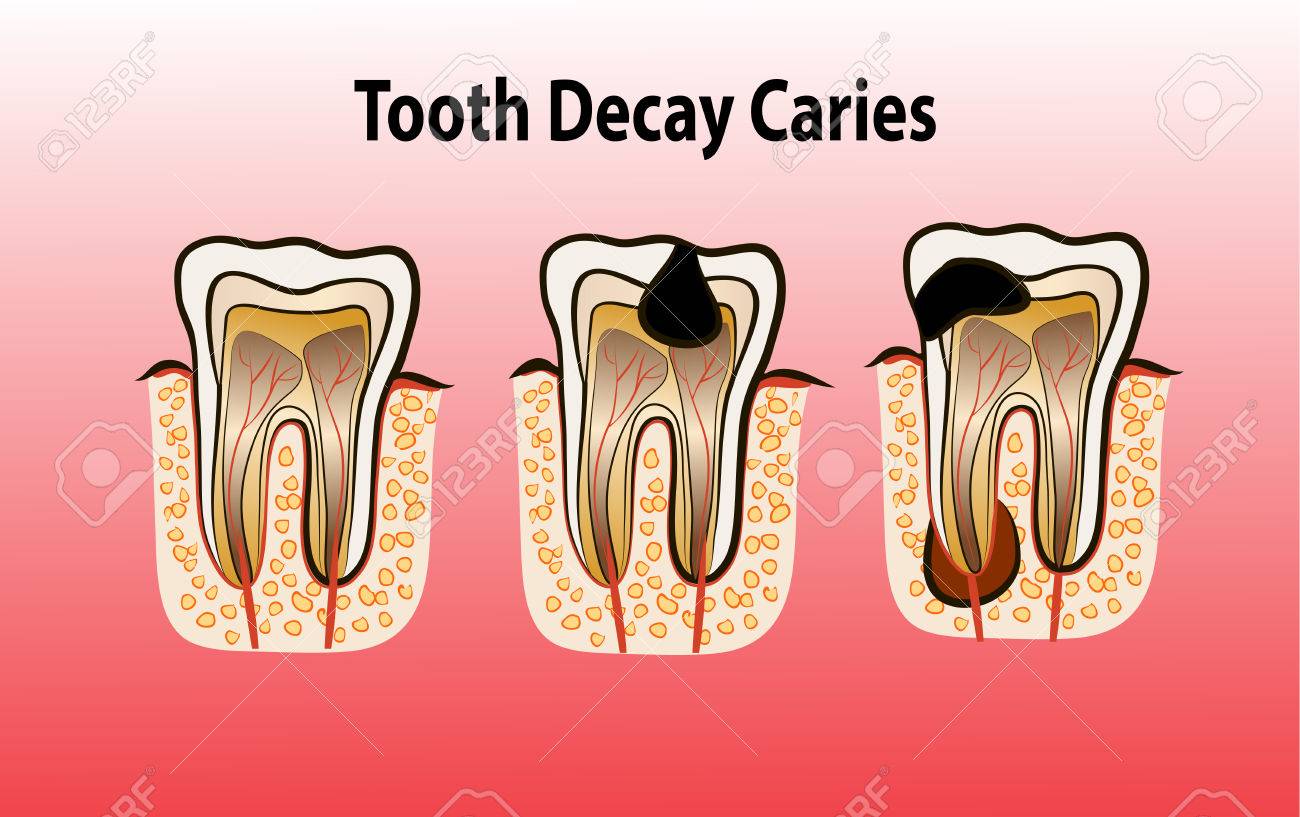

Stages Of Dental Decay And Periodontal Disease | High Dosage

dental decay disease caries stages teeth

The 5 Stages Of Tooth Decay | News | Dentagama

tooth dental decay abscess stages caries dentagama phoenix pain pulp infection teeth bone like spread look mouth periodontal severe enamel

Tooth dental decay abscess stages caries dentagama phoenix pain pulp infection teeth bone like spread look mouth periodontal severe enamel. Symptoms and treatments of dental caries. Stages of dental decay and periodontal disease